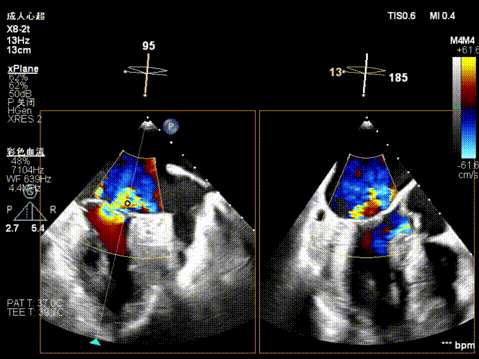

X-plane视窗可见二尖瓣病变区脱垂,重度偏心性返流.

3D enface view示二尖瓣P2P3区瓣叶脱垂,偏心性返流

Vmax=185cm/s 平均跨瓣压差为5mmHg